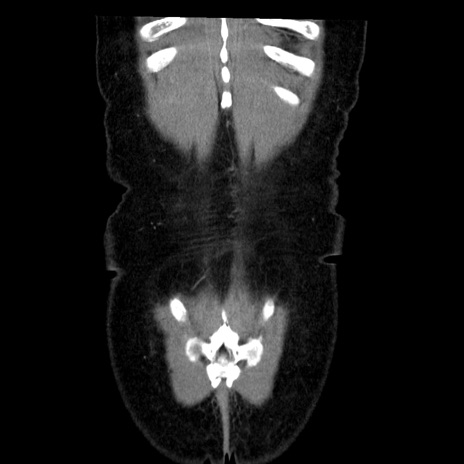

症例6(冠状断像)

【症例】50歳代女性

【主訴】下腹部痛

【現病歴】本日朝より下痢2回あり。 昼食を食べた後、嘔吐3回、下腹部痛認め、症状軽快せず、当院救急搬送。

最終食事:本日昼(生ものなし)。 昨日の夜、刺身を食ぺたとのこと。周囲に同様の症状の者なし。普段、排便は毎日あるとのこと。

【既往歴】卵巣癌術後(8年前に当院で卵巣摘出)

【身体所見】 意識清明、腹部:平坦、腸蠕動音→、やや硬、下腹部自発痛・圧痛あり、反跳痛あり、筋性防御なし。

【データ】WBC 16000、CRP 0.01